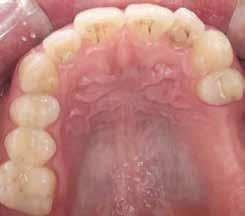

Digitális intraorális scan

Egy héttel a második műtét után intraorális szkennelést végeztünk Medit i500 scannerrel (Medit), a gyártó szkennelési protokollját követve (7. ábra). A gyógyulási csavarok eltávolítása után CERALOG scanbodykat (PEEK-titánötvözet csavar) helyeztünk el az implantátumokba. A fogszín meghatározását digitálisan, a Rayplicker (Borea) segítségével végeztük. A protetikai pótlás tervezéséhez poliphenilszulfon felépítményeket alkalmaztunk. Minden koronát digitálisan rendeltünk ugyanabból a fogászati laboratóriumból, és kerámiakoronákat választottunk minden esetben.

A koronák átadása

Átlagosan két héttel a szkennelés után a koronákat felhelyeztük, PEEK felépítményeket használtunk. Az összes koro-

na csavarozhatóan készült el. Mivel a négy páciens szigorúan a bioholisztikus megközelítés mellett döntött, a hat titán felépítménycsavart hat aranycsavarra (Holisticor csavarok) cseréltük ki. Ezeket az aranycsavarokat maximum 15 Ncm nyomatékkal húztuk meg. Titáncsavarok használata esetén legfeljebb 25 Ncm nyomatékot kell alkalmazni. A cég ajánlásának megfelelően az összes csavart legalább 5 perc elteltével újra meghúztuk a megfelelő nyomatékkal (15 Ncm). A csavarokat PTFE szalag védte, a fennmaradó csavarnyílásokat a cirkóniakoronával megegyező színű kompozitanyaggal fedtük. Az okklúziót ellenőriztük, és szükség esetén beállí-

tottuk (az okklúziós koncepciók alapján az implantációs pótlások nem voltak vezető fogak, és csak könnyű érintkezéseket alakítottunk ki, amelyeket artikulációs papírral ellenőriztünk). A páciensek instrukciókat kaptak a megfelelő szájhigiénére vonatkozóan, összpontosítva a fogköz kefékkel történő tisztítására. Végső kontroll röntgenfelvétel készült. A PEEK felépítmény nem radioopák, így az implantátum és a korona közötti távolság könnyen meghatározható a röntgenfelvételen: a felépítmény megfelelően illeszkedik az implantátumban, ha az implantátum válla és a korona alsó széle közötti rés 0,55 mm a röntgenfelvételen (8–11. ábra)

Minden páciens elégedett volt a kezelés eredményével, a funkcionális és az esztétikai eredmény egyaránt kielégítő volt. Az egyetlen megjegyzés – a teljes kezelés hosszú időtartama – a felső állkapocs esetében volt. A meghosszabbított, öt hónapos csontintegrációs periódus miatt, a teljes

eljárás több mint hat hónapig tartott. A kezelő szemszögéből a gyártó szigorú előírásainak betartása mellett nem volt jelentős különbség a titánimplantátumok használatához képest. A felső és alsó állcsont fogainak pótlásában a CERALOG implantátumok megfelelő és stabil alternatívának tűnnek a titánimplantátumokkal szemben.